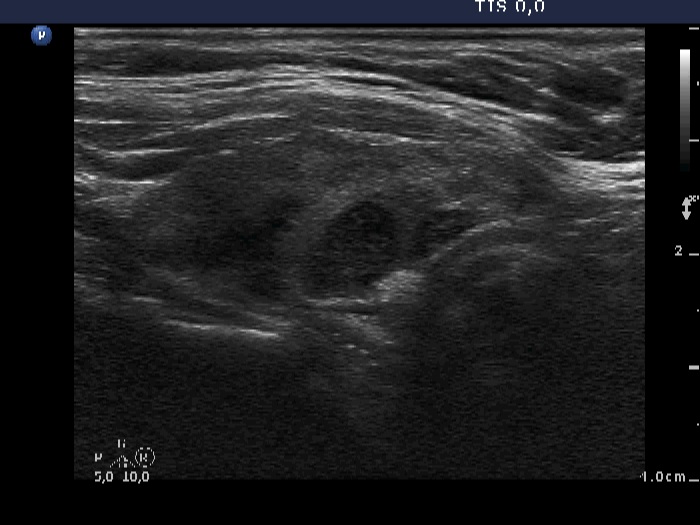

Chronic lymphocytic thyroiditis - Case 38.

Follow-up examination 5 years later (ultrasonographic picture 5)

Left lobe, longitudinal scan. The hypoechogenic area located in the dorsal part of the lobe remained unchanged.